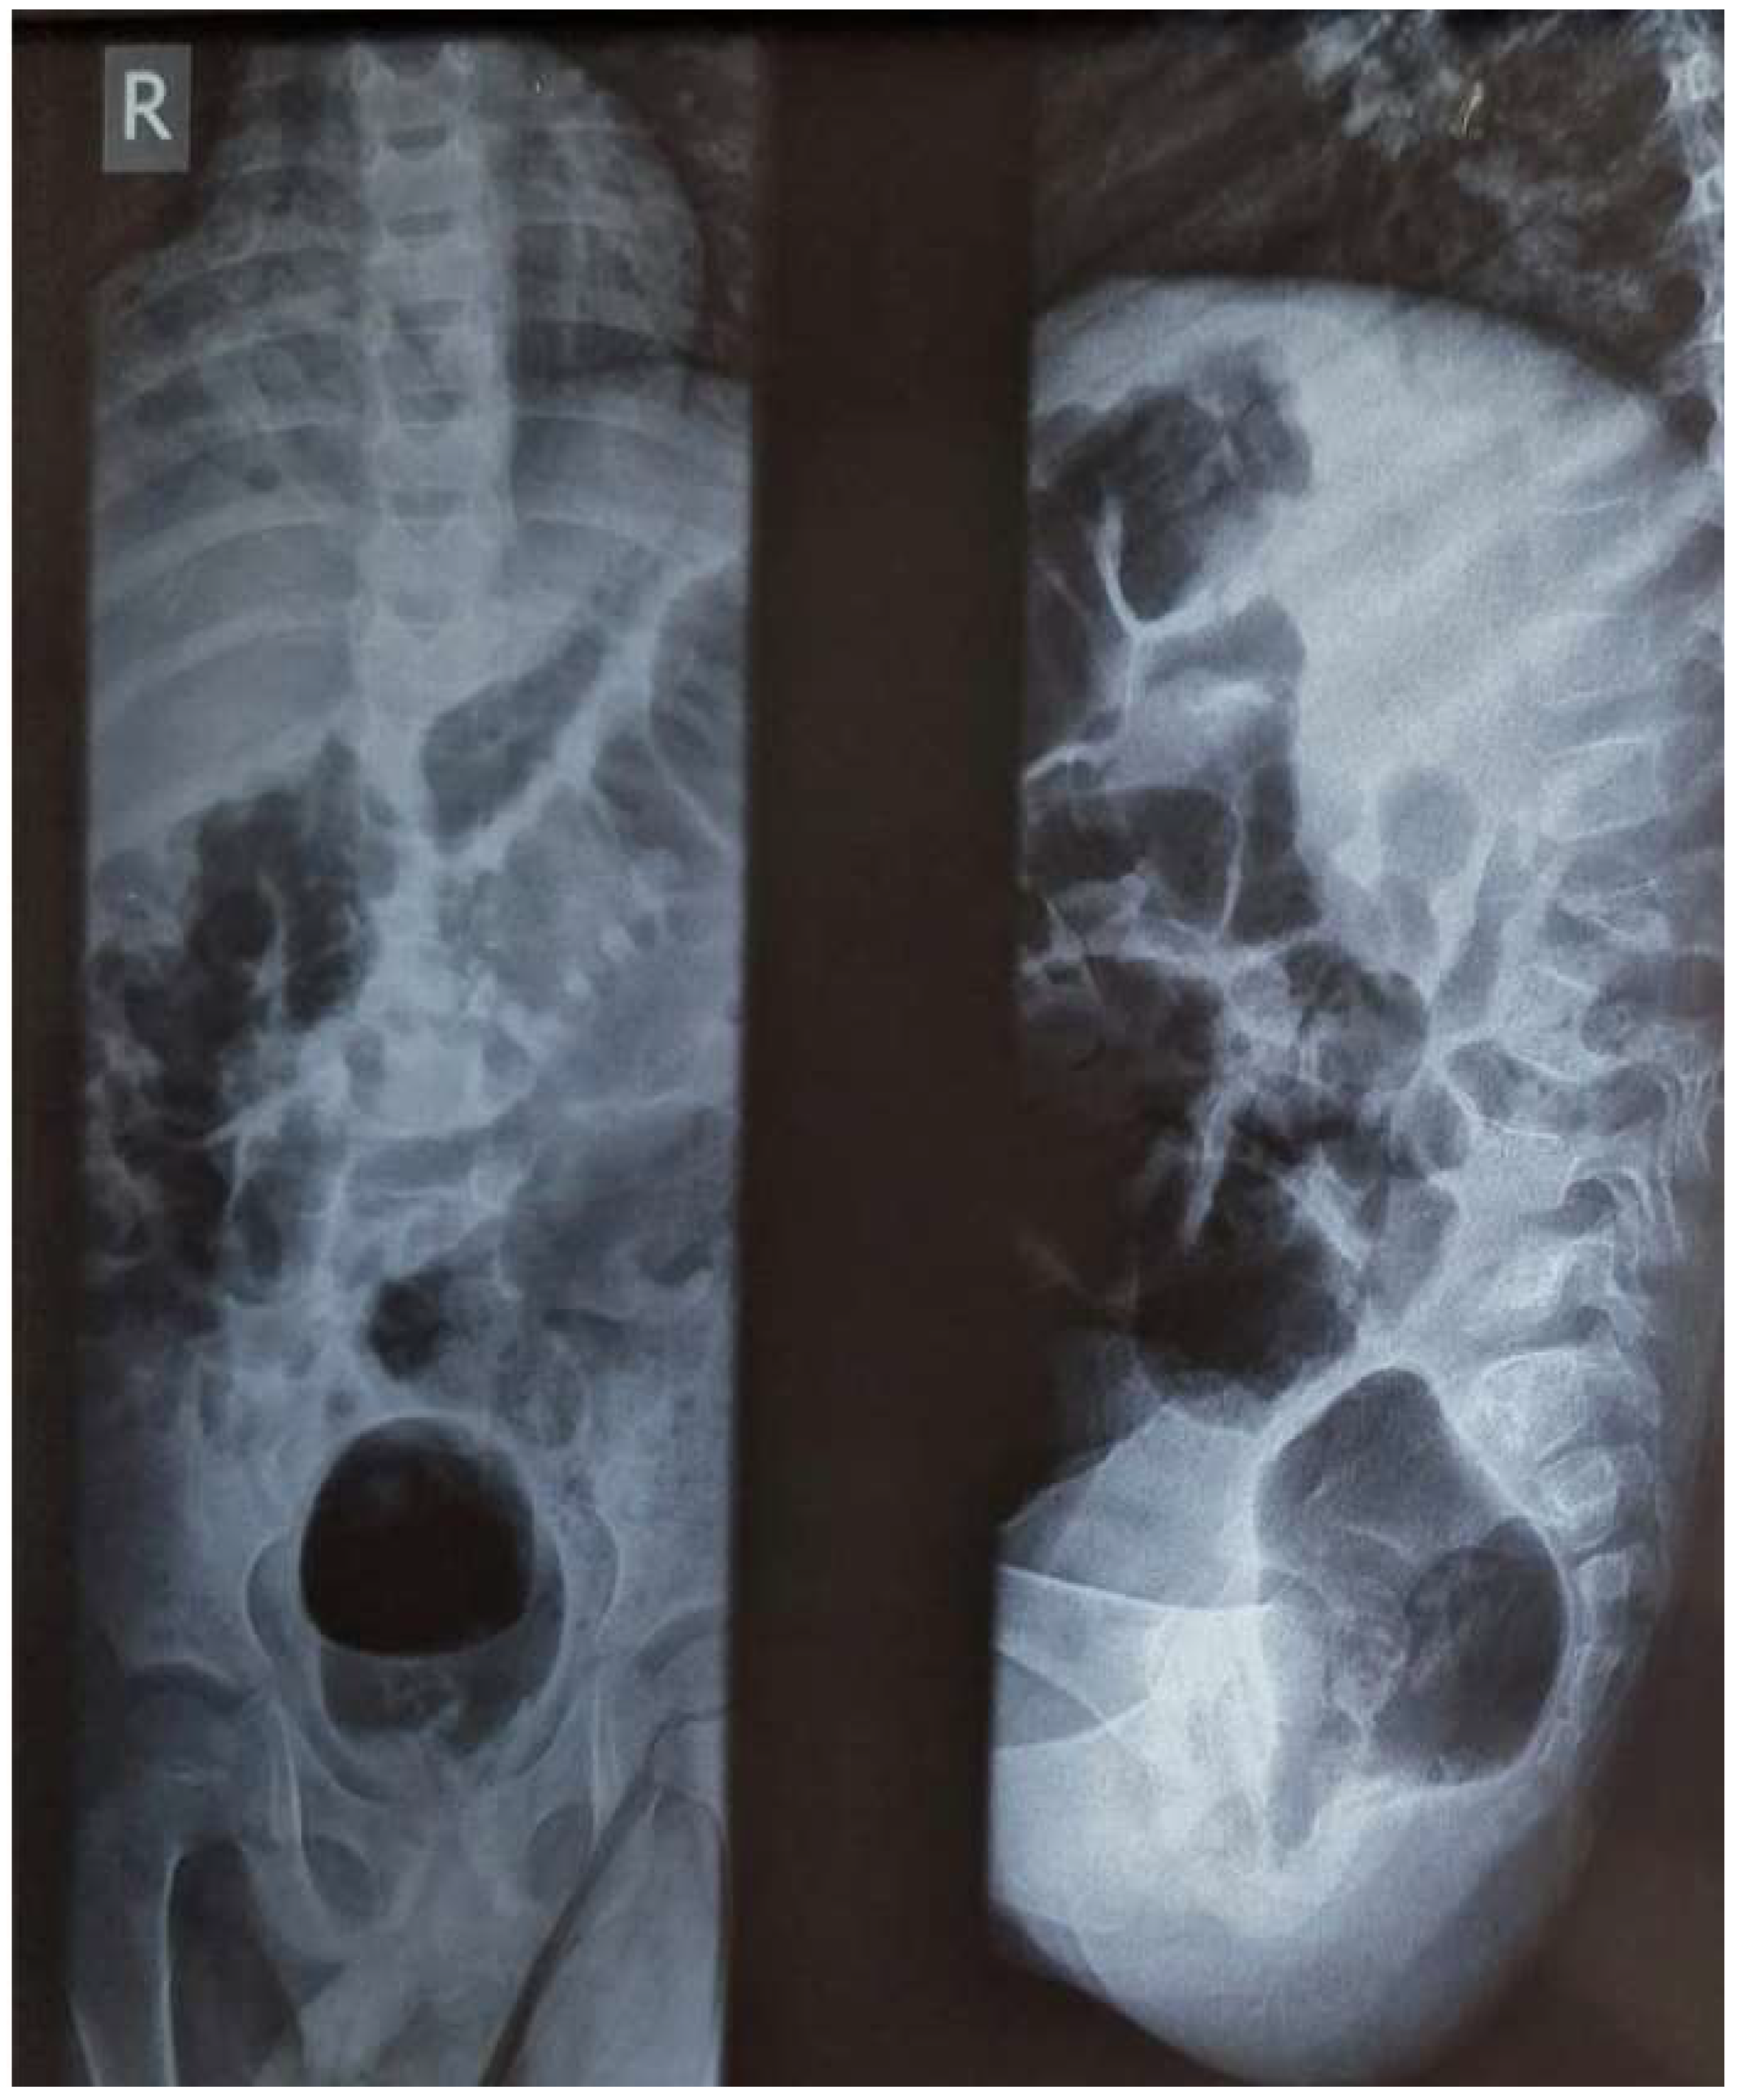

Successful Management, in a Low-Resource Setting, of Disseminated Tuberculosis in a 3-Year Old Boy: A Case Report

2. Case Report